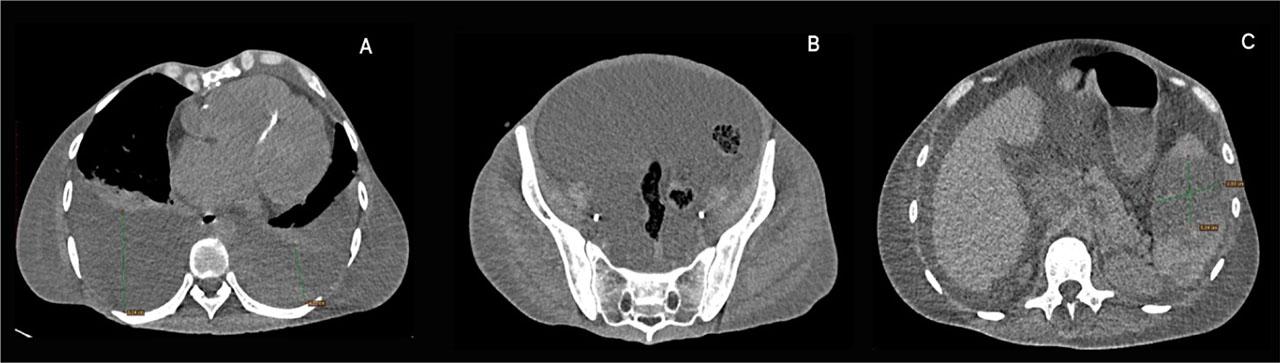

A subsequent non-contrast chest CT revealed large bilateral pleural effusions with partial lung atelectasis. In addition, a non-contrast CT scan of the abdomen and pelvis showed an enlarged liver without focal lesions, a large amount of ascites, and an enlarged spleen with multiple hypodense splenic lesions (suggestive of splenic infarction, which were also highlighted in the Urology Clinic through abdominal CT and abdominal ultrasonography) (Figure 1).

A. Chest CT scan: Large bilateral pleural effusions with atelectasis; Mild pectus excavatum with a Haller index of 2.28; B. Abdominopelvic CT scan: Large amount of ascites; C. Abdominal CT scan: Splenic infarcts